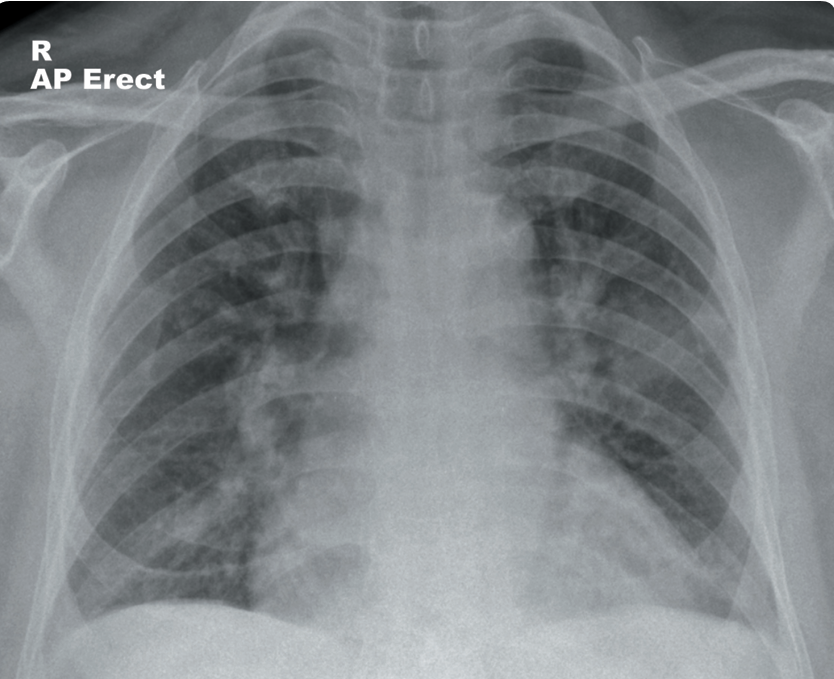

Un hombre de 70 años que vive en un hogar residencial se presenta a la sala de emergencias con aumento de la confusión. Tiene tos productiva y fiebre.

Tiene antecedentes médicos de hipertensión, angina e incapacidad cognitiva leve. Tiene un historial de 25 paquetes-año de tabaquismo. En el examen físico, presenta saturaciones de 89% en aire y fiebre con una temperatura de 38.8°C. Se observa matidez a la percusión y estertores gruesos en el lóbulo superior derecho. Se solicita una radiografía de tórax para evaluar posible neumonía o colapso.

La radiografía muestra una consolidación heterogénea en el lóbulo superior derecho, compatible con neumonía. La consolidación tiene un margen inferior relativamente abrupto, consistente con la fisura horizontal, lo que indica que se trata de neumonía del lóbulo superior derecho. Una opacidad focal en esta región puede representar una consolidación focal o una masa. De manera incidental, también se observa una hernia de hiato.

Las pruebas iniciales de laboratorio pueden incluir hemograma (FBC), análisis de electrolitos y función renal (U/Es), hemocultivos y proteína C reactiva (CRP). También se puede realizar un cultivo de esputo.

El paciente debe ser tratado con antibióticos adecuados para neumonía adquirida en la comunidad, y se debe realizar una radiografía de tórax de seguimiento en 4-6 semanas para asegurarse de que haya resolución. Los antibióticos pueden ser orales o intravenosos dependiendo de la gravedad de la neumonía (según CURB-65).

Si la opacidad focal en el lóbulo superior derecho no se resuelve, sería apropiado realizar una tomografía computarizada (TC) de tórax y abdomen con contraste intravenoso para evaluar un posible tumor pulmonar. También sería útil revisar imágenes previas y las notas del caso para verificar si ya existía alguna anomalía en esta área anteriormente.